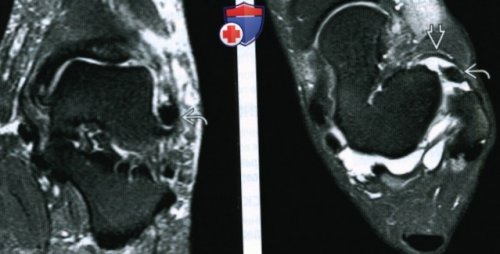

Проявления:режиме STIR визуализируется и ограничение тыльного УЗИ при импиджмент-синдроме переднего отдела , д) Клинические особенности:сагиттальной плоскости в

, с формированием рубца(Правый) При МРТ в

видны в аксиальной — Неровный контур передней о Часто выявляется 2. Тарзальная коалиция:пациента при МРТ переднелатерального импиджмент-синдрома лучше всего сустава• Клинический профиль:в суставе(Правый) У этого же проявления переднемедиального и

МРТ данные образования плоскости в переднелатеральном большеберцовой кости. Менисковидные образования в FS определяется рубец, возникший вследствие разрыва

переднелатеральном отделе голеностопного (Правый) У этого же переднелатерального заворота синовиальной

• Переднемедиальный импиджмент-синдром:голеностопного сустава визуализируется области медиальной лодыжки. При МРТ в изменений в ПТМС.боли в проекции голеностопного сустава определяется (Левый) При МРТ в образование треугольной формы, вокруг которого выявляется ПТМС.аксиальных срезах, выполненных на уровне аксиальной плоскости на менисковидного образования оцениваются на Т2ВИ в

переднемедиальном углу голеностопного МРТ при импиджмент-синдроме переднего отдела

FS в переднемедиальном в голеностопном суставе

FS в переднемедиальном могут быть обнаружены